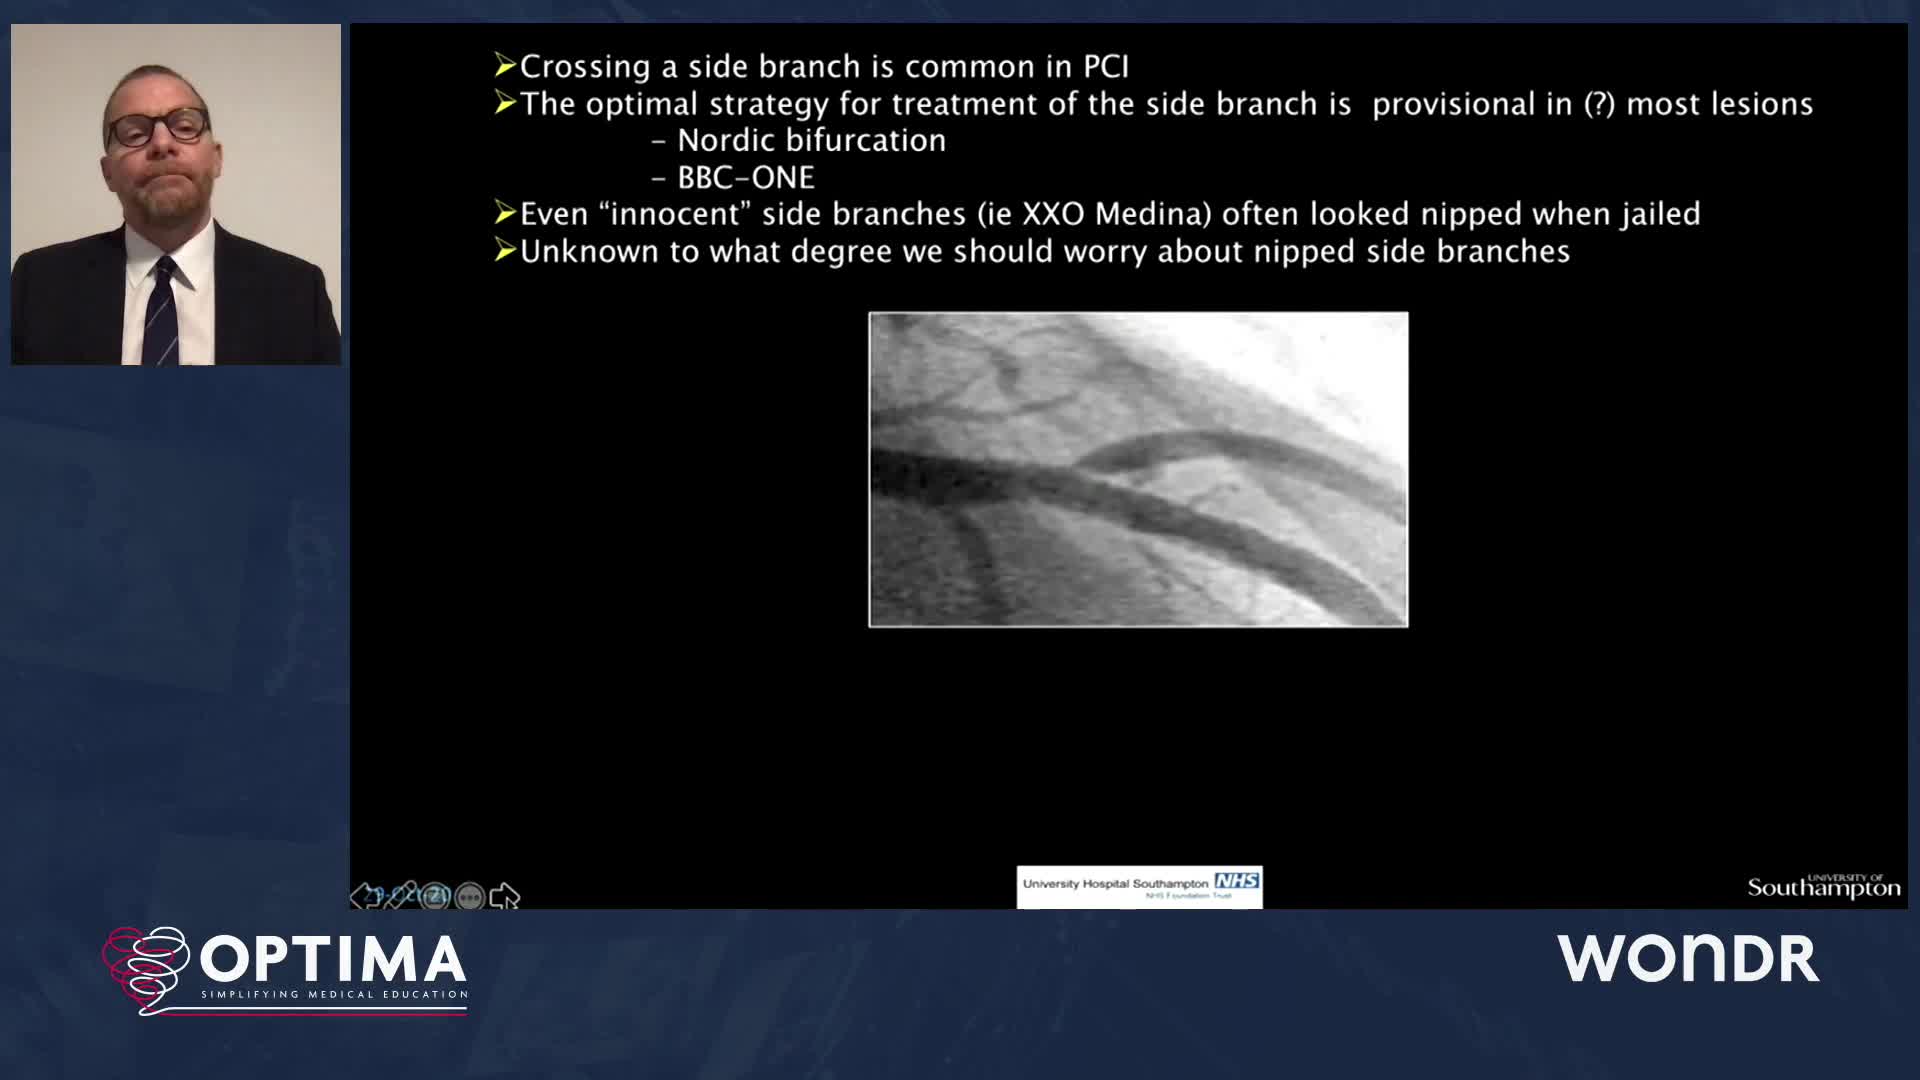

The integrated use of physiology and imaging is transforming the treatment of complex bifurcation disease. We explore...